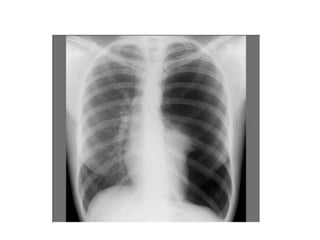

1. LA RX STANDARD DU THORAX

• Elle comporte des clichés thoraciques de face

et de profil en inspiration profonde comme de

pratique courante

• On peut aussi demander des rx de thorax de

face en expiration forcée ( devant des

épanchements minimes )

Apports :

• Affirmer le PNO

• Estimer la taille de l’épanchement

• discuter l’indication d’un drainage(CI si présence

de bulle d’emphysème )

• Analyser le parenchyme pulmonaire sous jacent

et du côté opposé

• Suivre l’évolution retour ou non du poumon à la

paroi

Résultats :

• hyperclarté avasculaire homogène périphérique

prenant tout l’hémithorax plus ou moins étendue.

• Rétraction du poumon s/f d’un moignon hyperdense

sur le hile avec distension des EIC et une netteté

anormale des côtes.

• La plèvre viscérale qui entoure ce moignon apparaît

sous forme d’un fin liséré opaque net comme tracé au

crayon